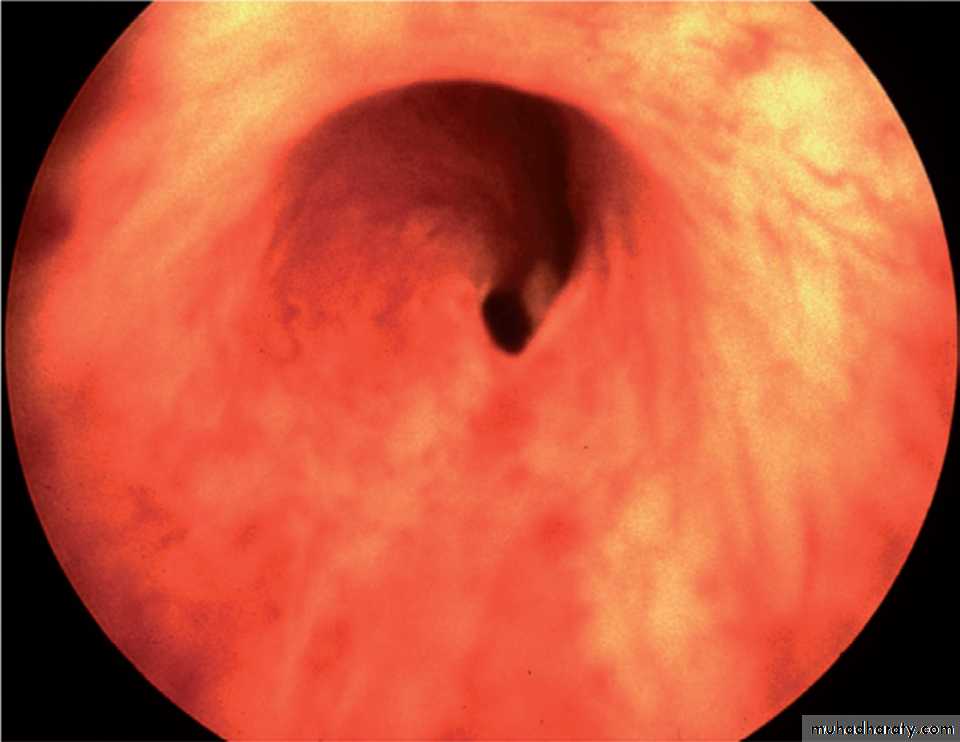

Cystoscope: by visulization of the valve

PUV (cystoscope)